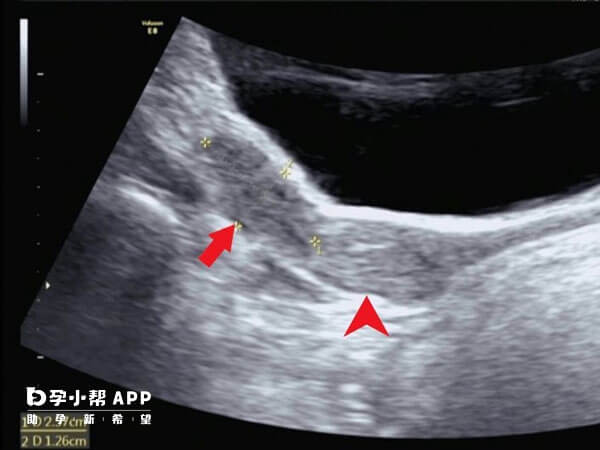

幼稚子宫属于发育畸形的一种,以目前的医疗技术并没有办法根治,幼稚子宫的处理办法要分为情况。